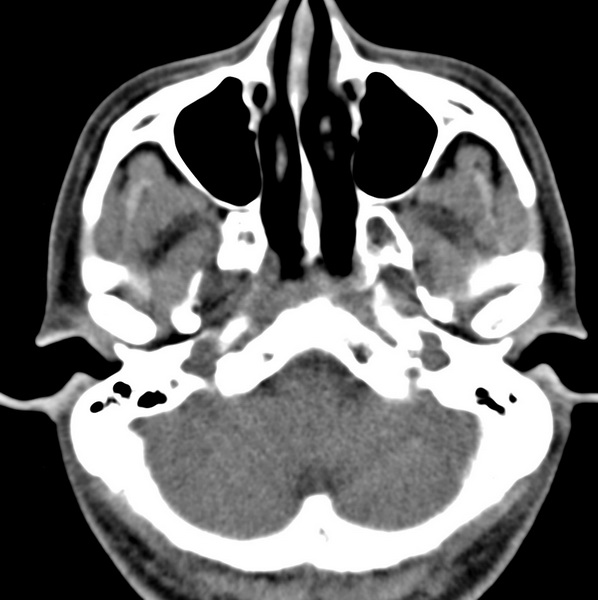

男、31、鼻咽部肿瘤放疗后请帮忙看看。

效果好,右侧破裂孔扩大,局部骨质缺损,为颅底骨质破坏。

1)鼻咽部肿瘤侵犯颅底放疗术后改变。2)左侧蝶窦炎。

咽后壁增厚,左侧咽鼓管隆突增大、咽鼓管咽口变浅,同侧咽旁间隙较窄。右侧颅底骨质破坏?为什么不在同一侧?

鼻咽部肿瘤侵犯颅底放疗术后改变.